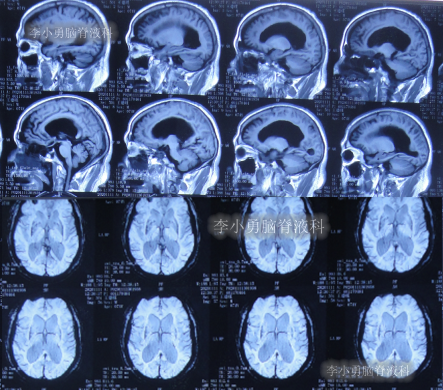

出院后再次转住入当地的第1家医院进行康复治疗,在该院康复治疗半年多的时间,不但没有持续好转,反而再次腰疼,走路不稳,且还出现了尿失禁的持续加重症状;治疗期间曾6次查头部影像(图-13、图-14、图-15、图-16、图-17)均示脑积水不断加重的趋势。

图-13:2021年5月22日头部核磁

图-14:2021年6月2日头部核磁

图-15:2021年7月24日头部核磁

图-16:2021年8月28日头部核磁

图-17:2021年9月28日头部CT